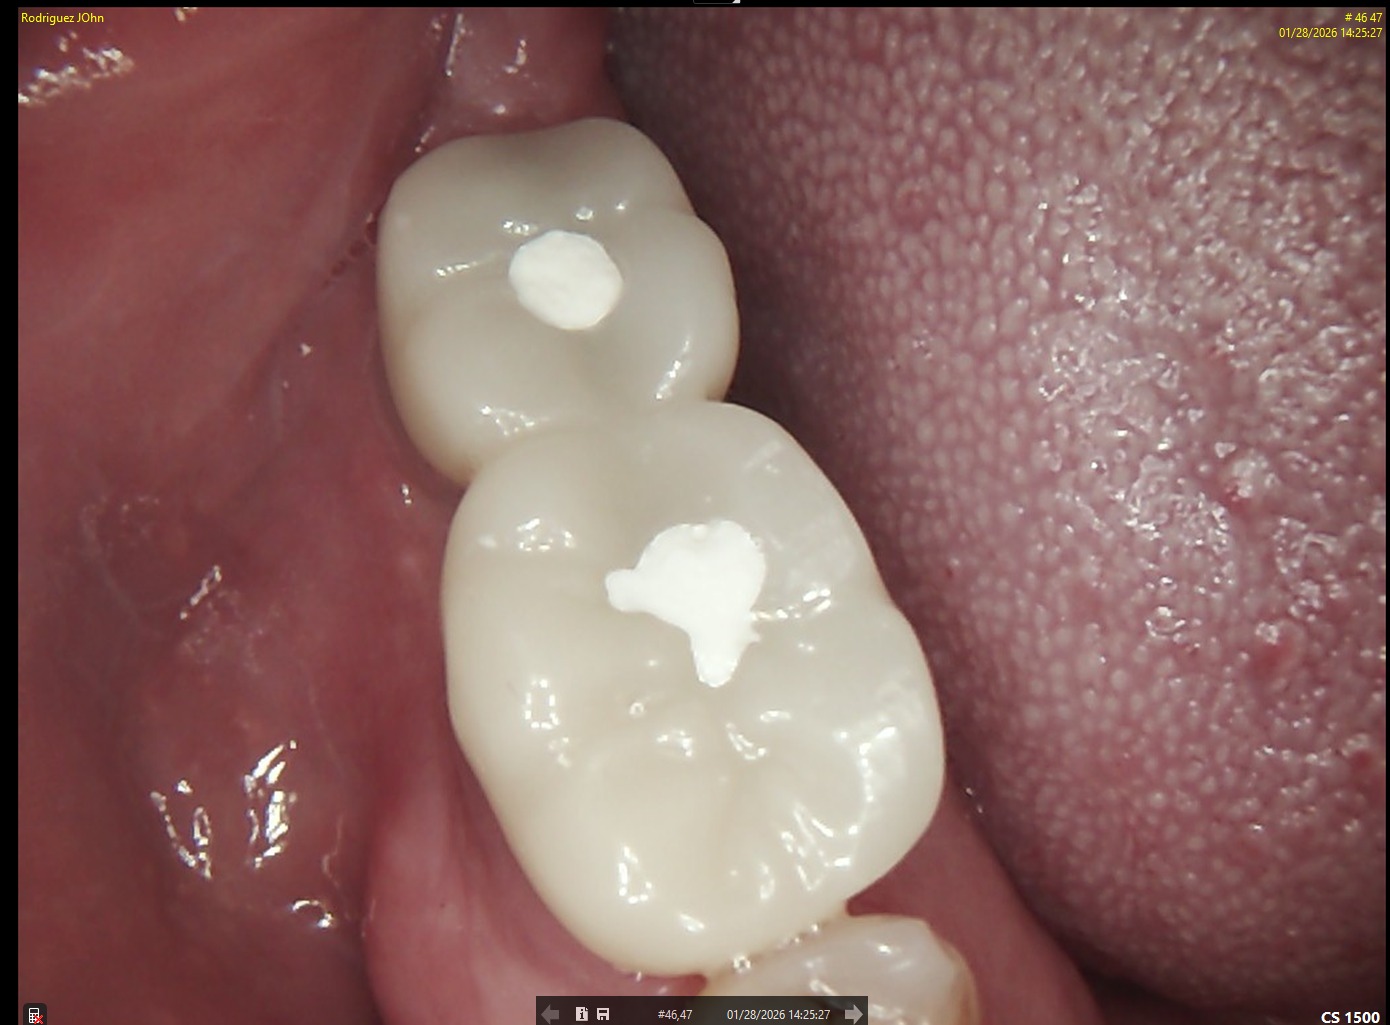

FOLLOW-UP - 2026

At the three-year follow-up:

• Peri-implant bone levels remained stable

• Soft tissues demonstrated healthy morphology and color

• The restorations maintained functional integrity under occlusal load

Both clinical and radiographic evaluations confirmed long-term hard and soft tissue stability, validating the treatment protocol and implant system used.